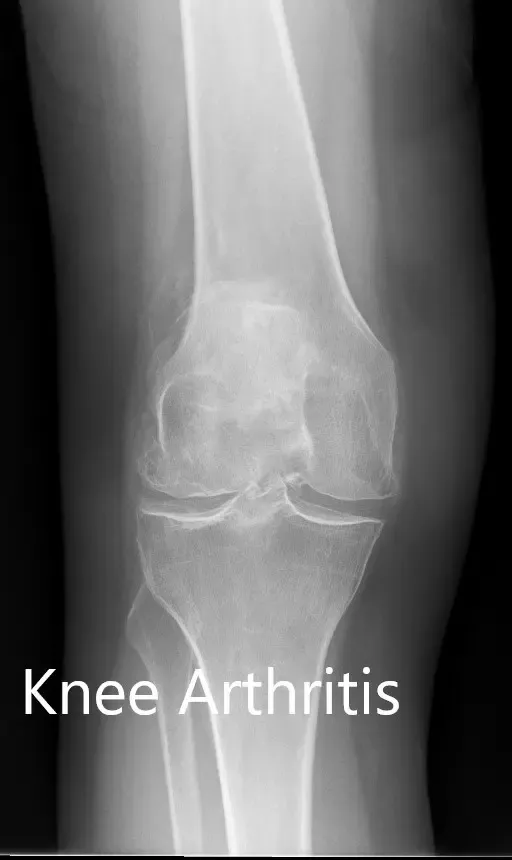

Los estudios de imagen realizados revelaron osteoartritis tricompartmental severa en ambas rodillas. Teniendo en cuenta que su estilo de vida limitaba el dolor de rodilla y el agotamiento de opciones conservadoras de manejo, le recomendaron un reemplazo bilateral de rodilla. Se le consideró candidato para un reemplazo total de rodilla personalizado. Él estuvo de acuerdo con el plan.

Radiografía preoperatoria que muestra la vista AP de la rodilla izquierda y la derecha respectivamente